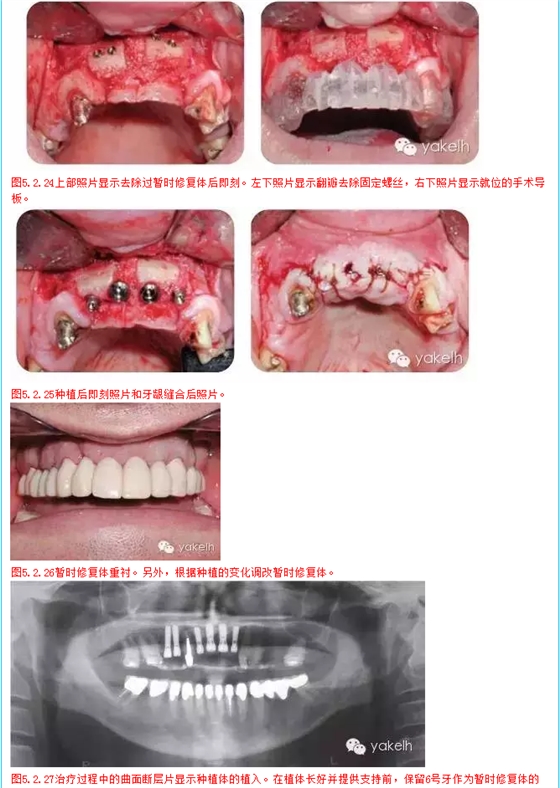

1 在2天內(nèi)分2次全牙列暫時性修復(fù)

2 種植區(qū)口腔外科骨移植手術(shù)

3 調(diào)整和修改暫時修復(fù)體

4 牙髓治療和牙髓再治療

5 完成下頜牙治療

6 4,5,7,8,9,10號牙種植修復(fù),6號牙仍作為暫時修復(fù)體的基牙

7 待種植后愈合和骨整合,調(diào)整和維護暫時修復(fù)體

8 安置種植體基臺,拔除6號牙,制作種植體支持式暫時修復(fù)體

9 拔牙創(chuàng)愈合

10 最終的上頜修復(fù)體,2,3號牙為單獨修復(fù),4號至10號牙為種植固定橋,6號牙為橋體,11號至15號牙為牙支持式固定橋